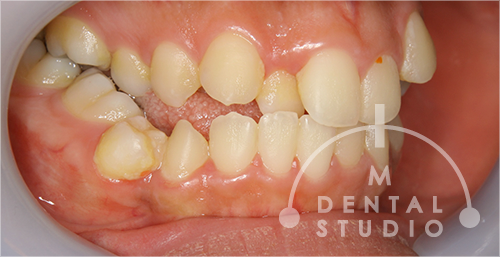

左側から見た写真(術前)

右側は激しい歯列のよじれがあります。